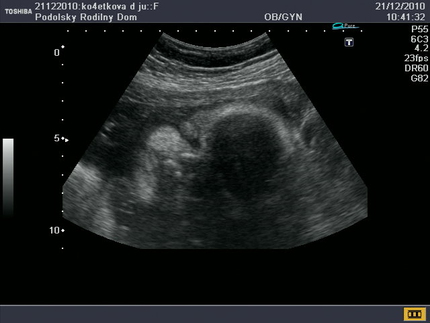

9 неделя беременности: малыш растет и развивается в предоставленных ему плацентой условиях полного комфорта. У него выделилась голова и начало формироваться лицо. Удлинились ручки, стали проявляться пальчики. И не просто проявляться. Именно на этом этапе возникает важное отличие эмбриона человека от других. Образовывающийся большой палец руки начинает разворачиваться таким образом, что оказывается прижатым к ладони с внутренней стороны. То есть формируется «противостоящий палец». Становится видна пуповина. В это же время окончательно складывается эмбриоплацентарное кровообращение. Начинает работать маточно-плацентарный барьер, то есть ваш организм включился в обеспечение безопасности будущего ребенка. А еще ваш ребенок начал с этого периода расти в два раза быстрее.

Кроме того, на этом этапе начинают различаться половые органы мальчиков и девочек, правда, они такие крошечные, что их еще не разглядеть даже во время УЗИ.

Также, маме может быть интересно и то, что плод в свои девять недель от зачатия уже умеет глотать — глотательный рефлекс считается одним из наиболее ранних и развивается уже сейчас, у малютки размером до 5 см и весом в 15 граммов.